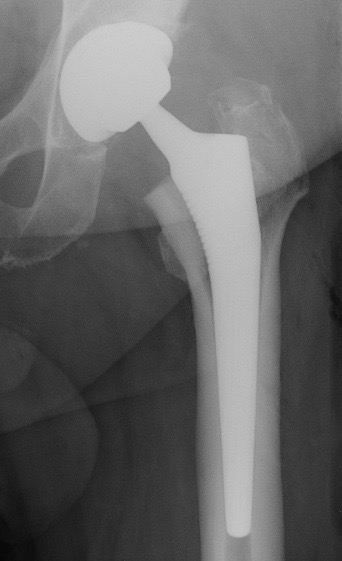

C. PTH avec polyéthylène et tige cimentée